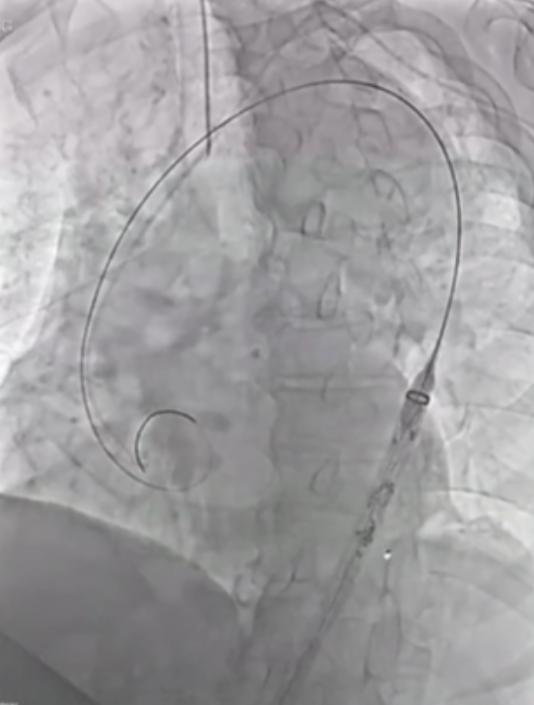

在近端密封区选择上,通常需向近端延伸25-30mm以实现更优密封效果,而定制器械凭借开窗设计,能有效增加密封长度。定制化支架技术也至关重要,支架必须精准定位,标记移动易引发开窗错位;同时要做好旋转控制,否则支架旋转不良会提升逆行夹层风险。一旦出现开窗对齐问题,可能导致I型内漏,且长期处理难度大,需借助更复杂的穿通技术纠正分支位置。

深圳设计的支架同样亮点十足。它具有短输送尖端的特点,无需跨越主动脉瓣,部署过程简单,且不需要进行严格的血压控制。支架配备两个平行侧支,搭配低剖面8-9F桥接支架,在接入方式上,采用右臂入路结合左颈动脉小切口的方式,为手术操作提供了便利,也有望为患者带来更优的治疗体验。